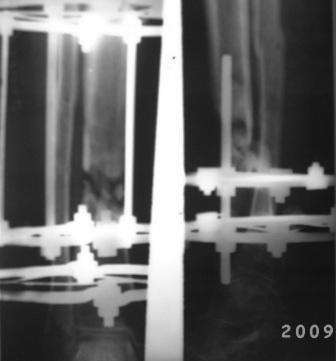

Уважаемые коллеги. Обратился б-ной 39лет, ДТП 8-мес назад, о/оскольчатый перелом костей правой голени, в ЦРБ произведена ПХО раны, остеосинтез спицами и проволкой, гипсовая повязка, со слов б-ного рана зажило первично, гипсовая повязка переложена несколько раз, но сращения не наступило, 2 мес назад КДО аппаратом Илизарова, срашения нет, после обратился к нам. Локально: признаков воспаления, лимфостаза нет, п/о рубец небольшой, сгибательная контрактура г/с сустава. Р-снимки прилагаются. Наш план.1. Перемонтаж аппарата, устранение смещения, остеотомия в/з б/берцовой кости с постепенным низведением до полной компрессии в обл ложного сустава. 2. БИОС с рассверливанием к/м канала. Уважаемые коллеги, помогите советом! Можеть быть сначала резекция концов л/с и потом низведение. или костная пластика? Или после завершения удлинения через какое время рекомендуется БИОС? С уважением Абдурашид.

Хотелось бы увидеть снимки голени на протяжении, и, если можно, с более высоким качеством. Неплохо бы сделать сравнительные снимки для сопоставления со здоровой голенью. По представленным картинкам очень трудно оценить состояние концов отломков и величину дефекта.